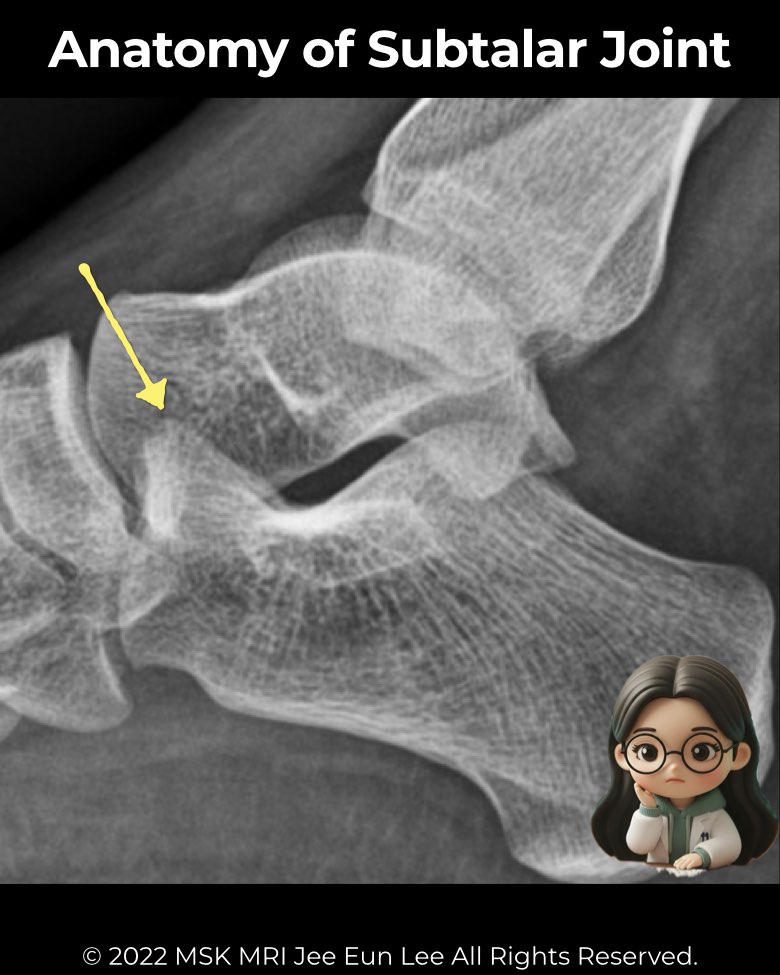

The subtalar joint (talocalcaneal joint) is vital for hindfoot stability and mobility.

- Posterior facet: largest, best seen on lateral radiographs and CT

- Middle facet: on the sustentaculum tali, may communicate with the talonavicular joint

- Anterior facet: smallest, may merge with the middle facet